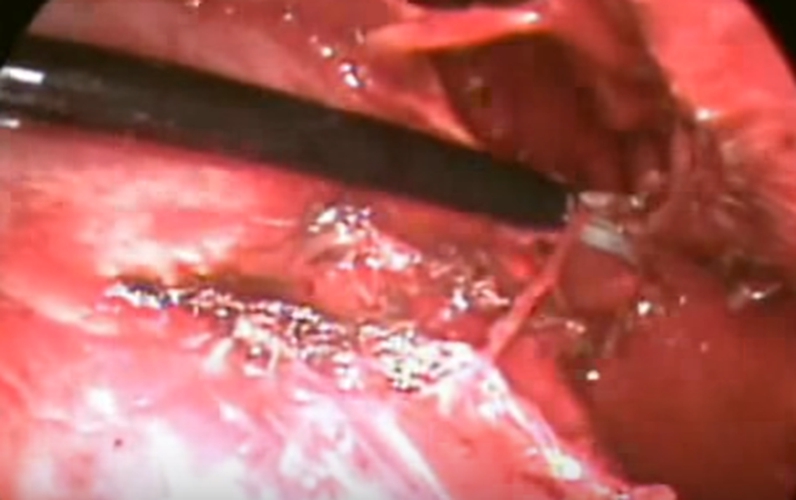

結核性胸膜炎胸腔鏡

結核性胸膜炎胸腔鏡的